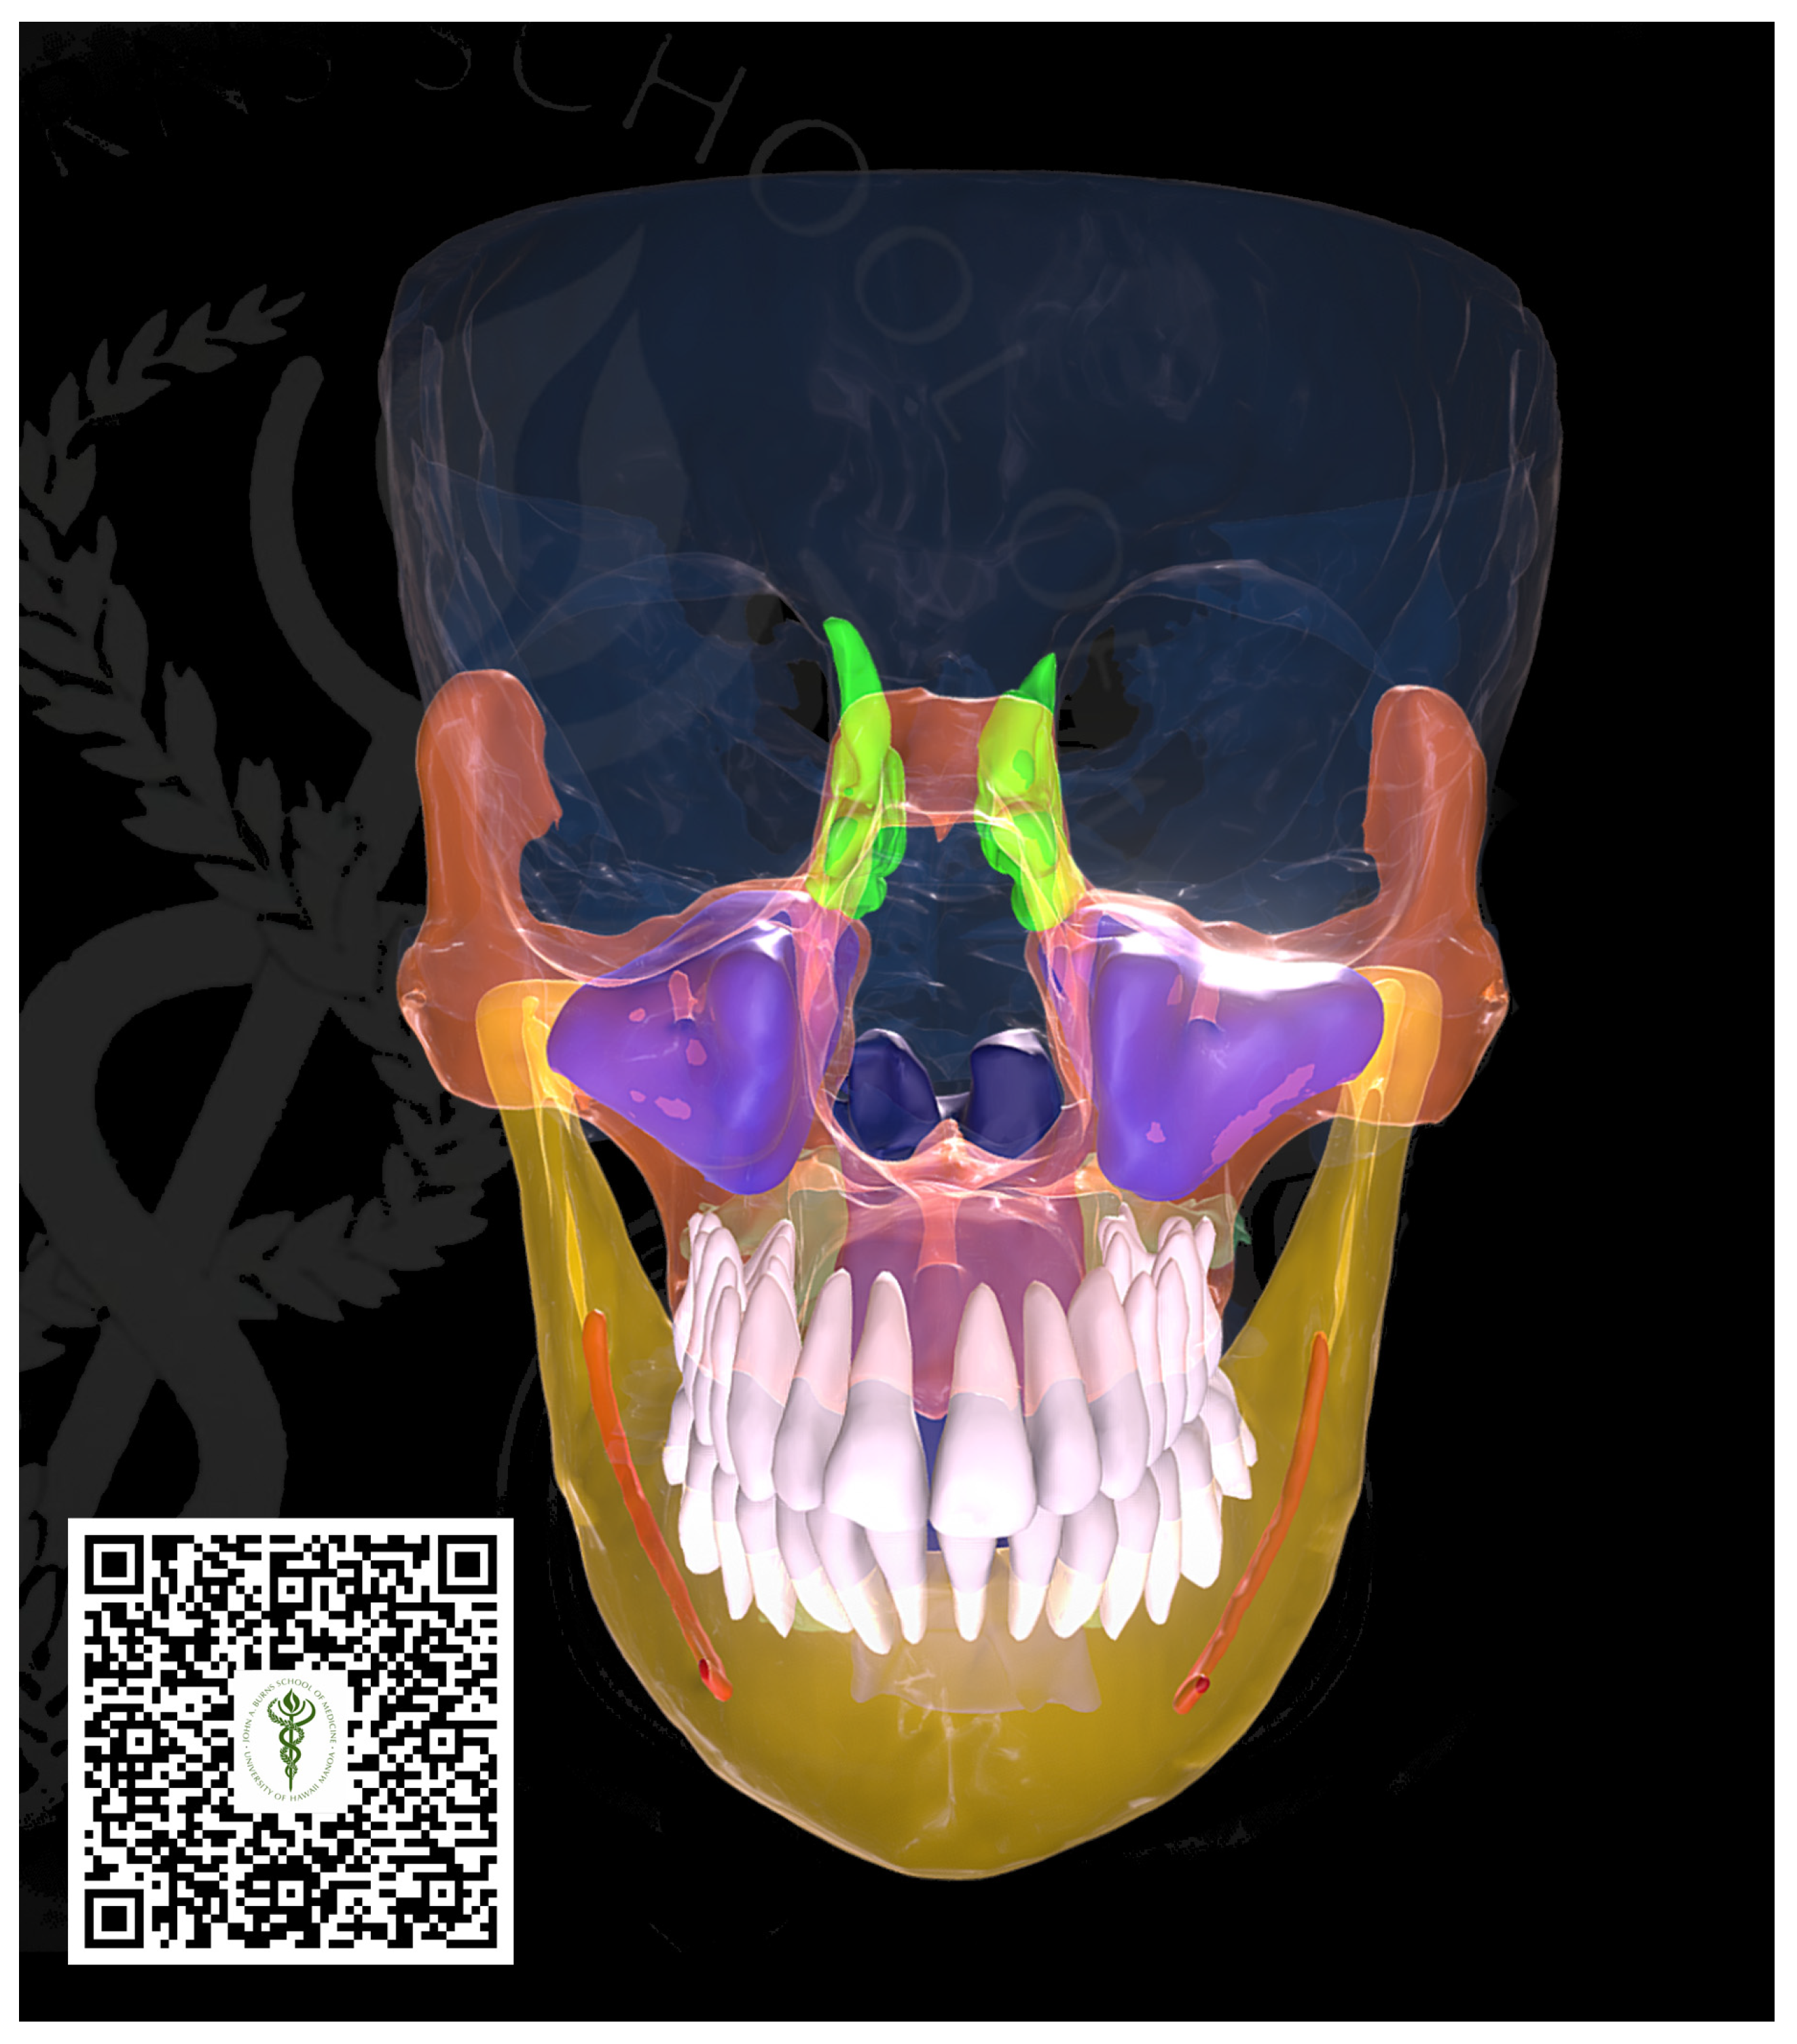

The creation of surface models was intended to facilitate visualization and exchange. The pertinent structures were delineated using the software application 3D slicer (specific version, location). A range of threshold values was specified, and tools such as region growing, smart split, and Boolean operators were utilized to encapsulate the relevant structures. The polymesh segments were exported in the STL format and imported into a Pixologic Zbrush. Subsequently, the topologized models underwent retopologization by projecting the surface information from the original data onto the subdividing models, and a surface polishing algorithm was employed to retain landmarks while eliminating noise and faceting from the corresponding segmentations. Any areas with excessive noise or distortion were edited manually. Texture “baking” and texturing procedures were executed using the Adobe Substance Painter. The models and textures were exported and uploaded to Sketchfab (http://www.sketchfab.com), accessed on 7 February 2022, where additional material properties, lighting, and annotations were defined and applied. These were also integrated into Unity, where they could be viewed using various XR hardware systems, including Hololens, zSpace, and WebGL apps (see Figure 2).

Figure 2.

Three-dimensional surface model for visualization. The model presents some radiographic findings such as aplastic frontal and sphenoid sinuses and hypoplastic ethmoid sinuses. By scanning the barcode below using a phone camera, the 3D surface model can be manipulated on the phone screen.